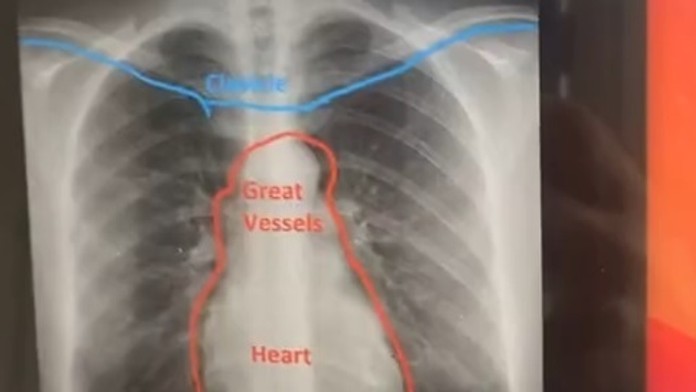

Tínedžerku (19) dlhšie trápil kašeľ. Následné röntgenové vyšetrenie odhalilo nečakanú anomáliu

Zároveň ju však už dva mesiace trápil kašeľ, a tak sa rozhodla, že podstúpi röntgenové vyšetrenie. To odhalilo, že má srdce na opačnej strane hrudníka.

Doktori zistili, že má infekciu pľúc, a tak ju následne poslali na röntgen. Tam jej lekárka povedala: „Je to trochu čudné, ale vedeli ste, že máte srdce nie na ľavej, ale na pravej strane hrudníka?“

„Začala som sa smiať, pretože som tomu, úprimne, neverila. Doktorka mi povedala, že sa to nazýva dextrokardia a že by som o tom mala informovať svojho lekára,“ uviedla Claire, ktorá o tom doteraz nevedela.

Dextrokardiou trpí menej ako jedno percento populácie. Mladá žena sa svojím príbehom pochválila na sociálnej sieti TikTok, kde video videli už takmer dva milióny používateľov.